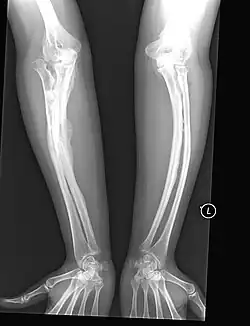

The main symptom of osteogenesis imperfecta is fragile, low mineral density bones; all types of OI have some bone involvement.[5] In moderate and especially severe OI, the long bones may be bowed, sometimes extremely so.[28] The weakness of the bones causes them to fracture easily—a study at the Endocrine Unit at the National Institute of Child Health in Karachi, Pakistan found an average of 5.8 fractures per year in untreated children.[29] Fractures typically occur much less after puberty, but begin to increase again in women after menopause and in men between the ages of 60 and 80.[1]: 486

OI type III causes osteopenic bones that fracture very easily, sometimes even in utero, often leading to hundreds of fractures during a lifetime;[24] early scoliosis that progresses until puberty; dwarfism (a final adult height frequently less than 4 feet or 120 centimetres); loose joints; and possible respiratory problems due to low rib cage volume causing low lung volumes.[5]: 1512

Diagnosis

Diagnosis is typically based on medical imaging, including plain X-rays, and symptoms. In severe OI, signs on medical imaging include abnormalities in all extremities and the spine.[97] As X-rays are often insensitive to the comparatively smaller bone density loss associated with type I OI, DEXA scans may be needed.[5]: 1514